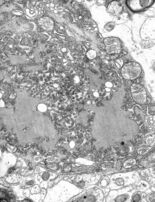

Chagas disease is also known as American trypanosomiasis. There are approximately 15 million people infected with Chagas disease.[18] Morbidity rates are higher for immuno-compromised individuals, children, and the elderly, but can be very low if treated early.[40] Chagas disease does not kill victims rapidly, instead causing years of debilitating chronic symptoms. It is caused by a vector-borne[41] protozoa[40] and spread by contact with Trypanosoma cruzi-infected feces of the triatomine (assassin) bug. The protozoan can enter the body via the bug's bite, skin breaks, or mucous membranes. Infection can result from eating infected food and coming into contact with contaminated bodily fluids.[40] There are two phases of Chagas disease. The acute phase is usually asymptomatic. The first symptoms are usually skin chancres, unilateral purplish orbital oedema, local lymphadenopathies, and fever accompanied by a variety of other symptoms depending on the infection site.[40] The chronic phase occurs in 30 percent of total infections[18] and can take three forms, which are asymptomatic (most prevalent), cardiac, and digestive lesions.[40]

Chagas disease can be prevented by avoiding insect bites through insecticide spraying, home improvement, bed nets, hygienic food, medical care, laboratory practices, and testing.[40] It can be treated with medication, although these may have severe side effects.[40] It can be diagnosed through a serological test, although the test is not very accurate.[18]